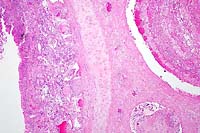

40x

- Case 24-2. Lung. Alveolar septa are thickened by hypertrophic

type II pneumocytes, and alveoli are often filled with cellular

debris and rare multinucleate giant syncytial cells bearing bright

pink intranuclear and intracytoplasmic inclusions.